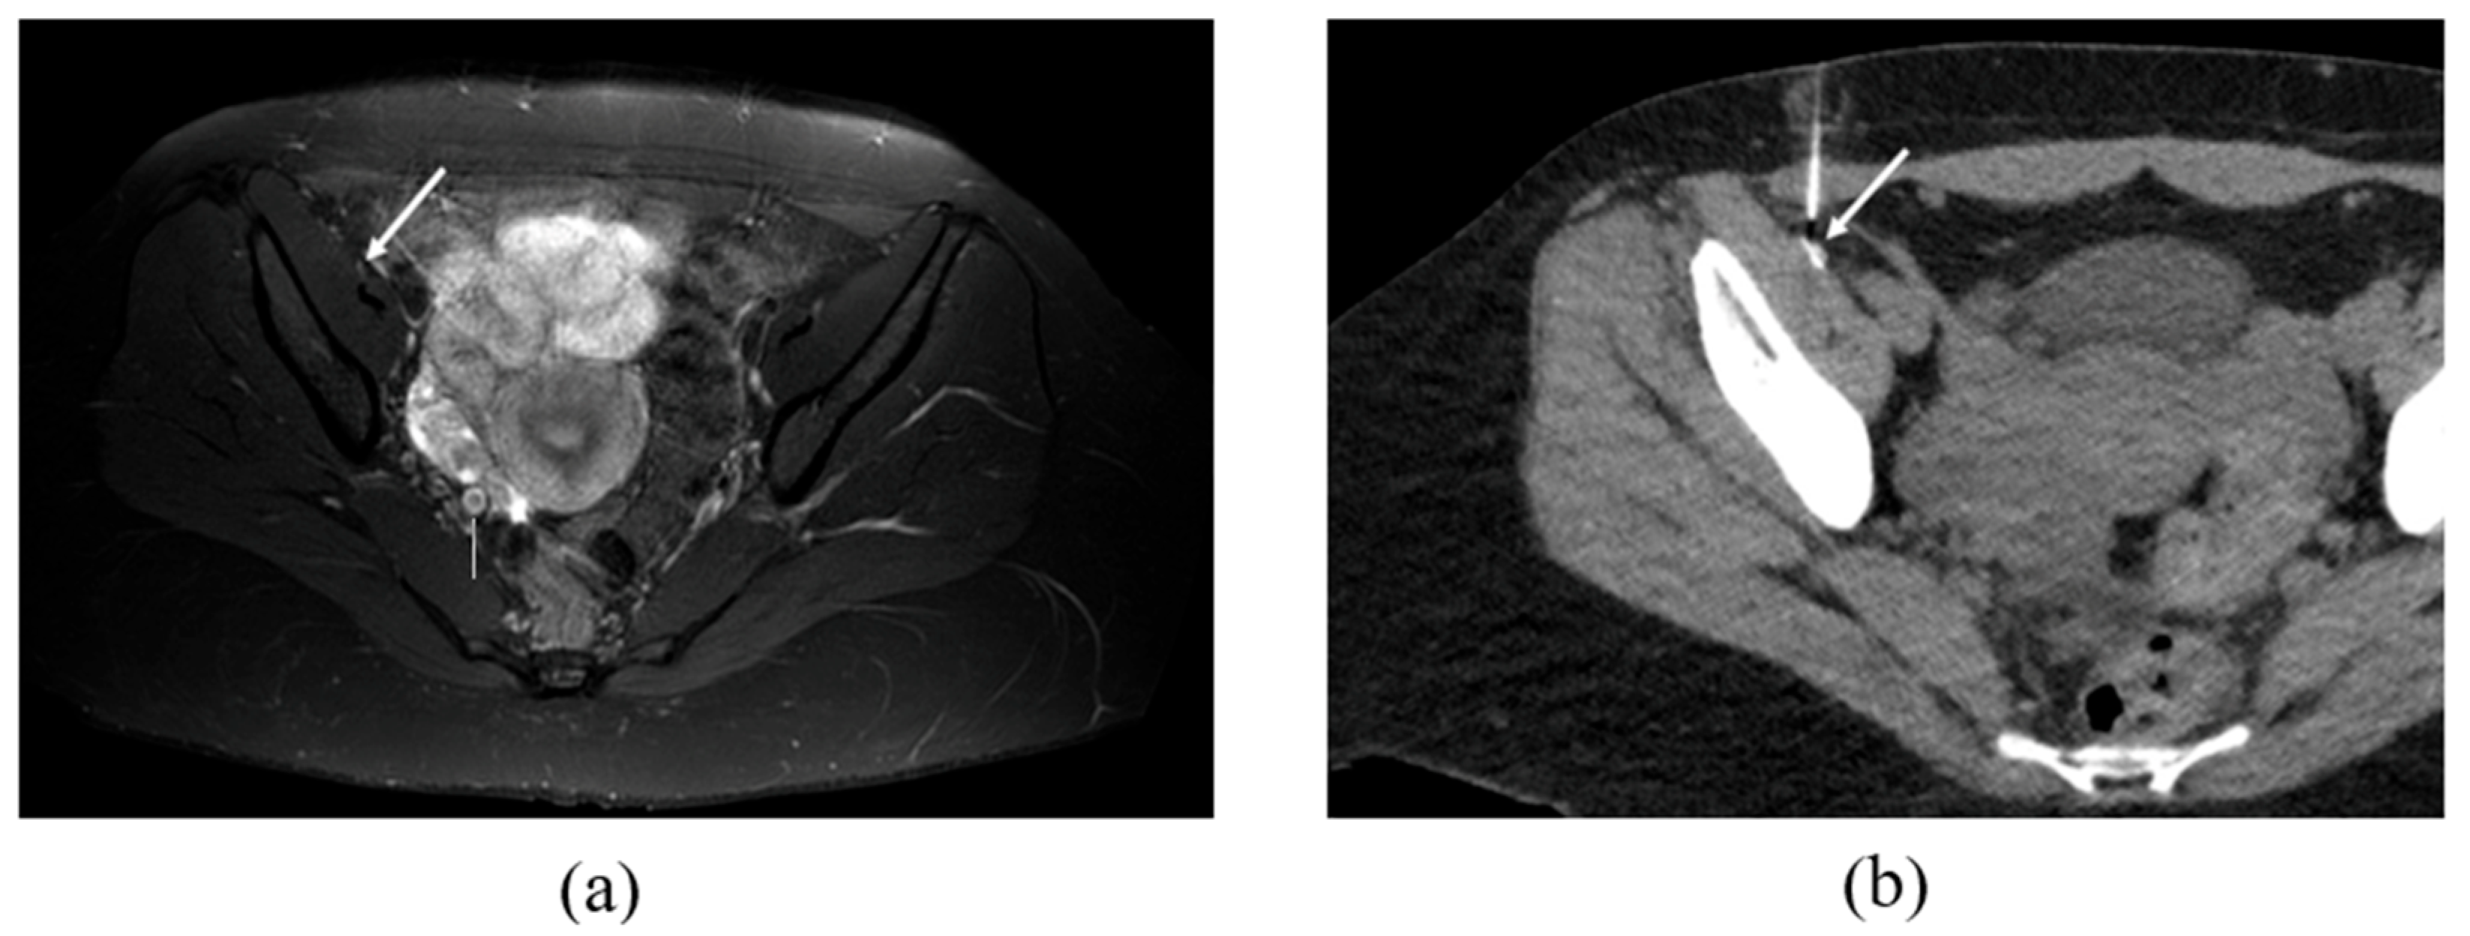

2.2. CT-Guided Procedures

3.2. MRN Findings